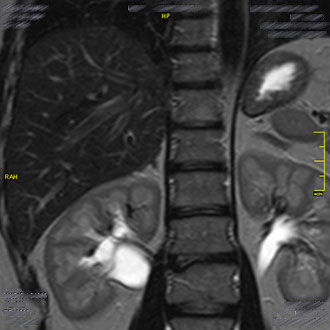

Die MRT der Nieren und Nebennieren bietet eine exzellente Darstellung der Harnorgane.

Sie wird zur Beurteilung von Nierenzysten, Nierentumoren, Nierenanomalien oder Veränderungen des Nierenbeckenkelchsystems eingesetzt.

Auch die ableitenden Harnwege lassen sich mithilfe moderner MRT-Technik gut darstellen.

Im Kernspin Zentrum Köln werden so Erkrankungen frühzeitig erkannt und Therapien gezielt vorbereitet.